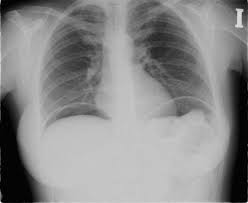

Que tiene este paciente y como se llama el signo?

Neumoperitoeneo, signo de ala de gaviota